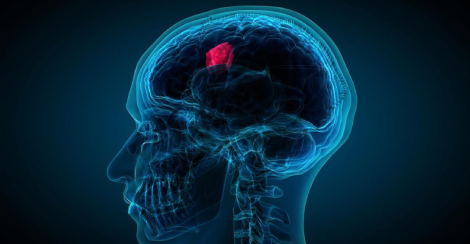

The brain tumor is a mass of abnormal cells into your brain that hinders its activities. There are different types of brain tumors. Some are benign (noncancerous) and some are malignant (cancerous). Any symptoms like new headaches, vomiting, vision blur, numbness, difficulty in balance, confusion, and seizures, etc. The brain tumor can also cause brain stroke. The tumor can be detected using methods like neurological examination, which includes checking vision, hearing, balance, coordination, strength, and reflexes. Another method is through imaging tests; mostly MRI Scan is used but some specialist use Computerized Tomography (CT). Depending on the location, size, and type of the brain tumor the treatment is done. Also, the amount of pressure put by a tumor on the vital part of the brain, whether the tumor is spread to the other part of the CNS and body as well as patient’s overall health and preferences are considered to decide the treatment.